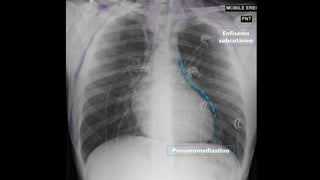

ENFISEMA SUBCUTÂNEO

TRAUMA É CAUSA MAIS COMUM!

OUTRAS CAUSAS IMPORTANTES:

Pneumotórax

Pneumomediastino

Enfisema intersticial pulmonar

Perfuração de víscera oca

Fasciíte necrotizante

Enfisema

subcutâneo